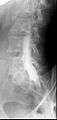

Computed tomography after conventional myelography. The overlap-free representation often allows a more secure assessment. The high density of contrast material may be troublesome in case of insufficient mixing prior to CT.